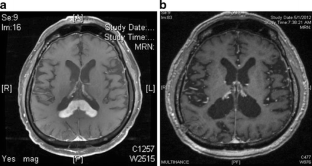

Figure 1